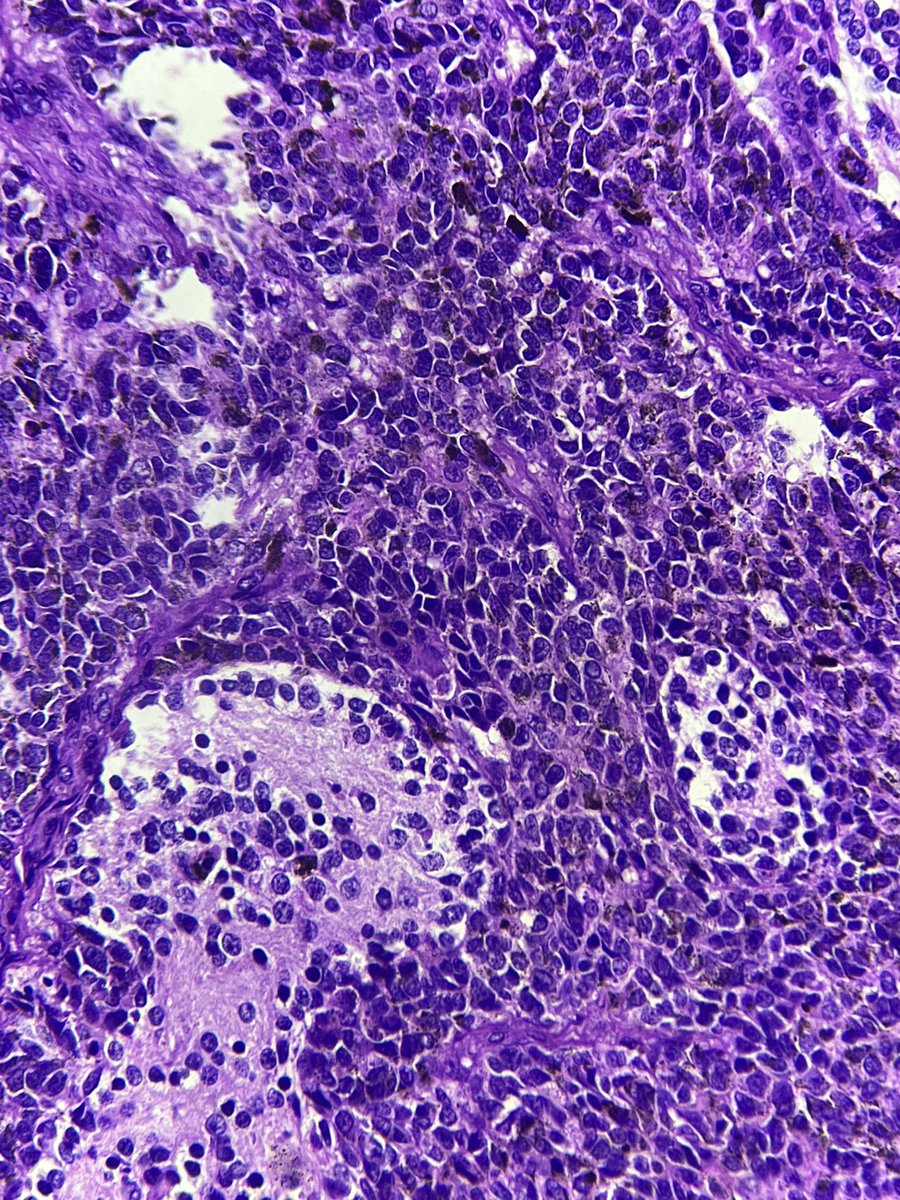

Placental Site Trophoblastic Tumor • RARE malignant trophoblastic neoplasm from intermediate trophoblasts • Mean Age: 31 • 2/3 cases follow full term pregnancy (median latency 12-18 months) • 🩺: Vaginal 🩸, uterine enlargement • ~25-30% may develop recurrent dz